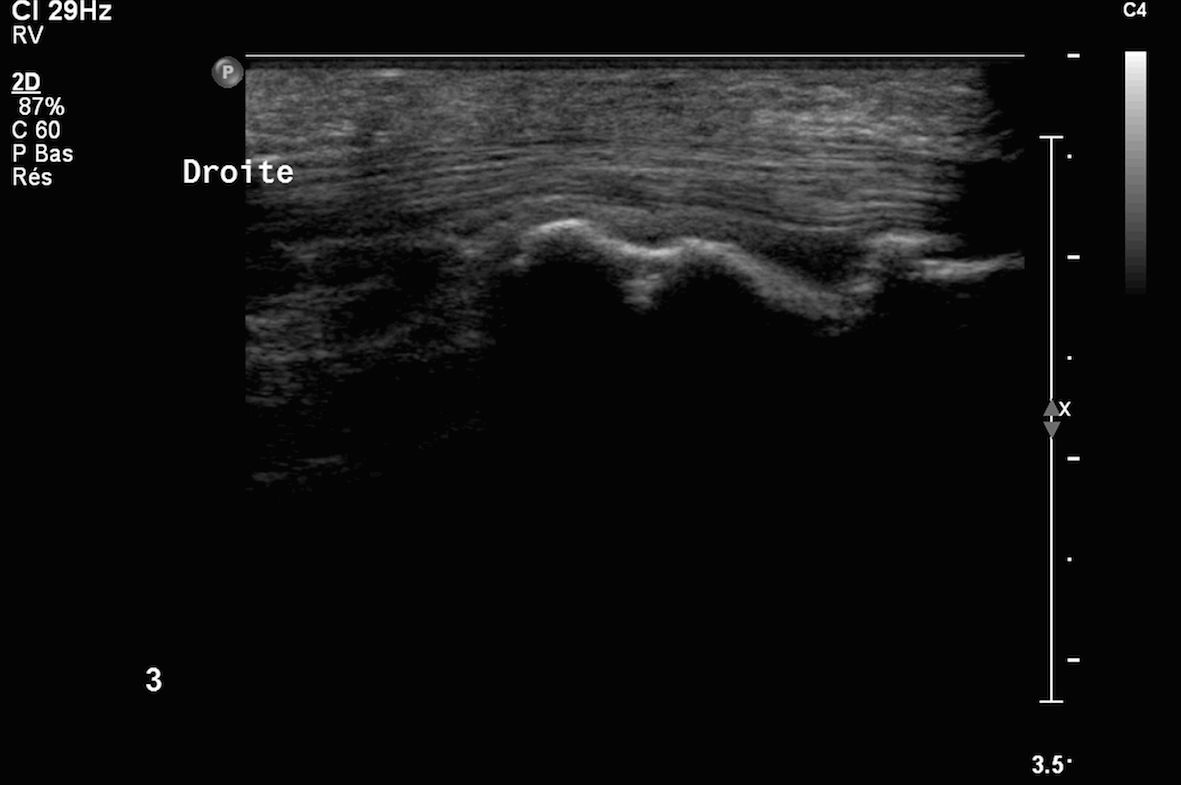

4Infiltration du tendon du tendon 3ième fléchisseur de la main (images 1 et 2) sous contrôle échographique

Images 3 et 4 visibilité du produit anti inflammatoire injecté sous deux incidences orthogonales en regard de la gaine péri tendineuse